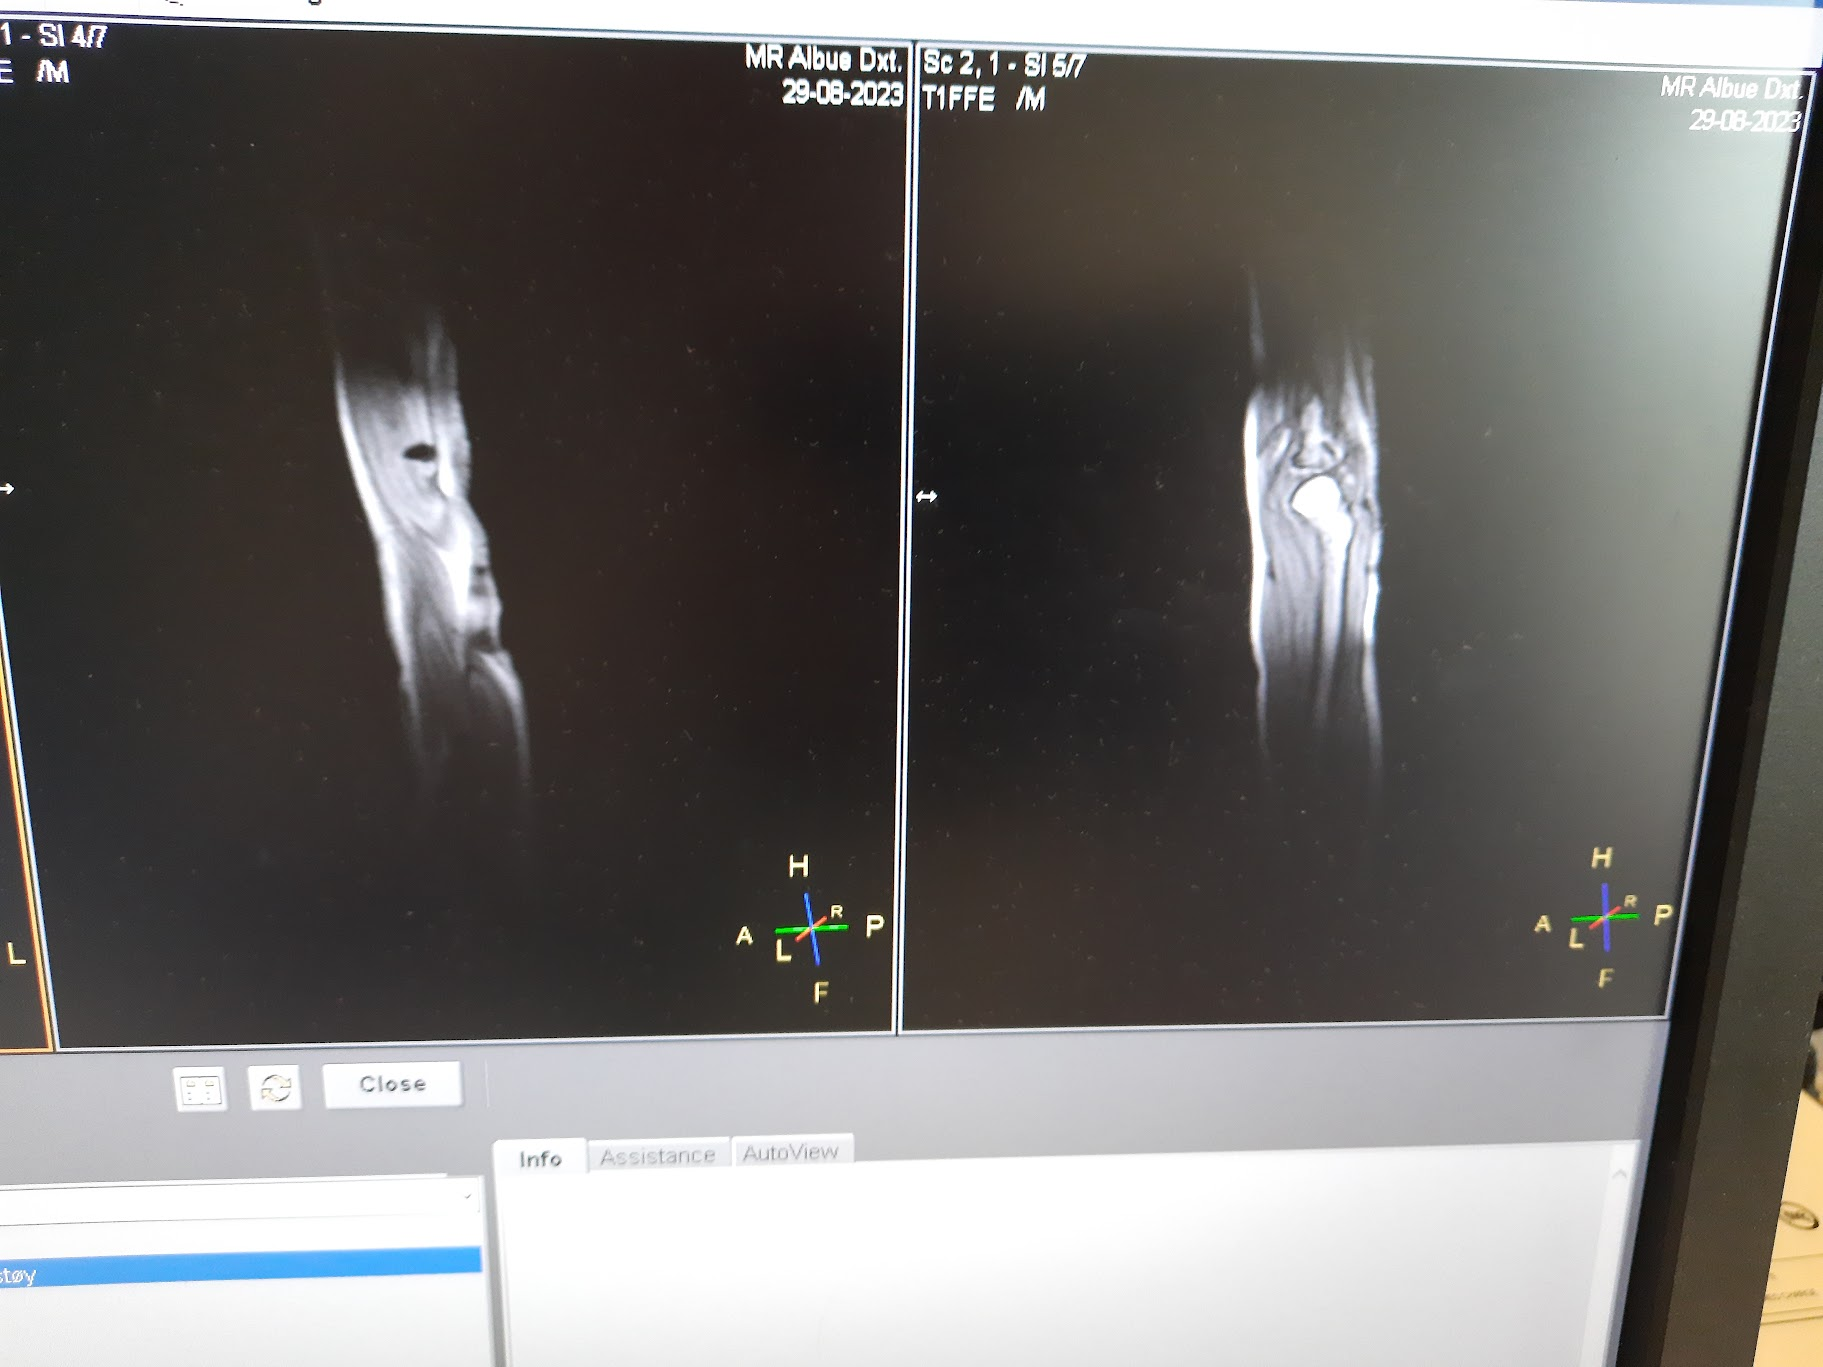

Моя лапка. Ничего непонятно, но очень интересно.